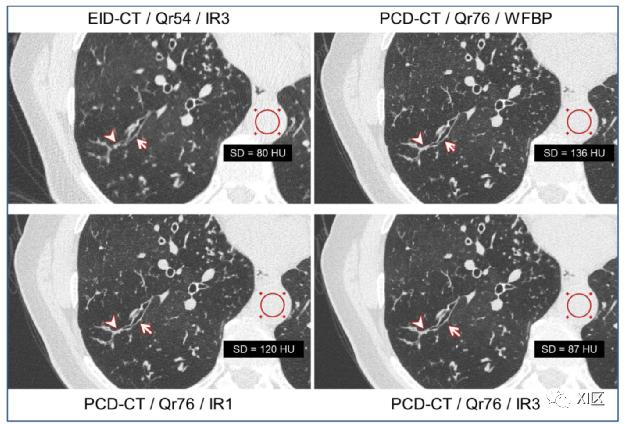

图13显示了在高分辨率胸部CT中使用光子计数探测器可实现的图像质量。

图13 EID-CT胸部图像(左上图)0.6 mm层厚,IR重建,以及用WFBP(右上图)和两种迭代强度(分别为1和3、左下和右下)以及0.6 mm层厚的同一患者的PCD-CT胸部图像。EID-CT和PCD-CT图像均显示右下叶支气管轻度扩张(箭头所示),并伴有外周分支。使用UHR模式的PCD-CT图像清晰地描绘了远端支气管周围分支处的粘液塞(箭头)。显示的ROI测量值是CT值标准差。显示窗宽/窗位=[1500/-600]HU。实际上,空间分辨率不仅取决于探测器的像素大小,而且还取决于X射线管的焦点尺寸,而焦点尺寸需要相应地减小。病灶越小,通常球管可用功率越小,这就限制了超高分辨率CT扫描的临床应用范围。此外,如果辐射剂量保持不变,分辨率的提高是以图像噪声增加为代价的。在所有情况下,增加患者的辐射剂量以补偿较高的噪声可能是不可接受的。因此,非线性数据和图像去噪技术将在利用光子计数探测器的高分辨率潜力方面发挥关键作用。